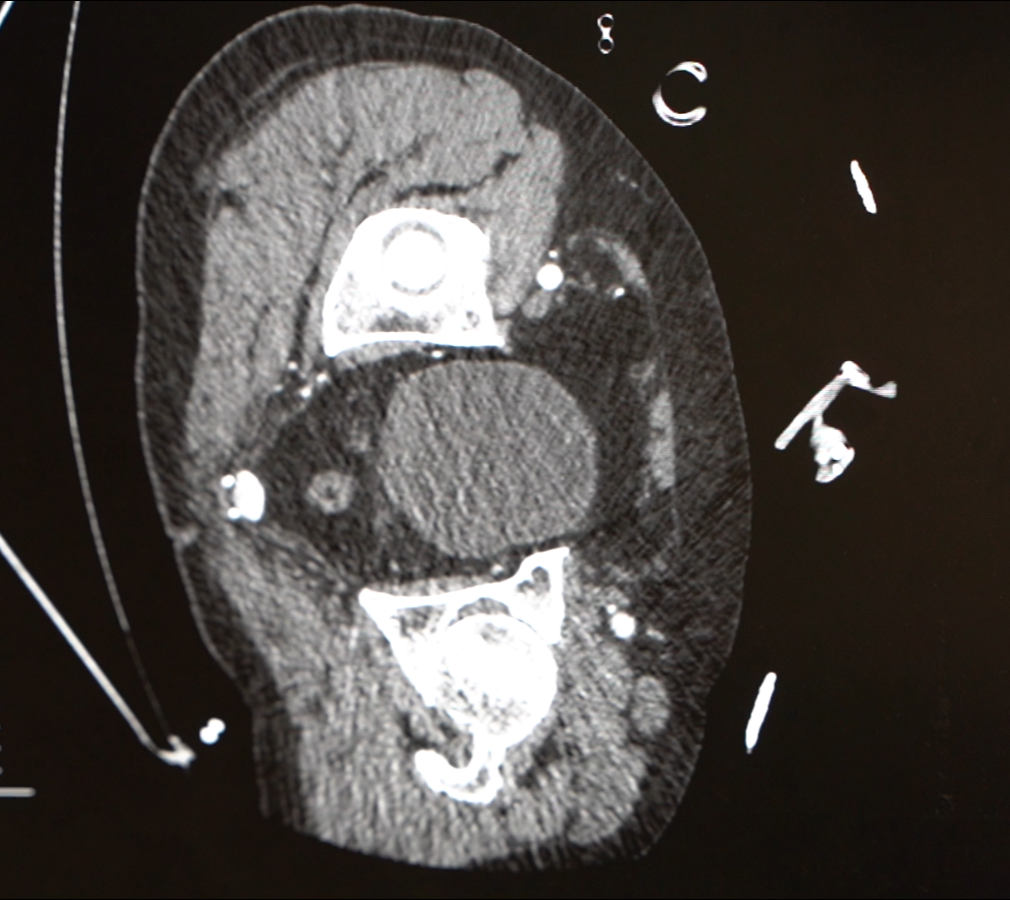

主动脉夹层就像藏在身体里的“水管炸弹”,医生解释:主动脉是全身最粗的血管,就像家里的“主水管”,一旦因为血压太高、长期劳累等原因出现分层撕裂,血液就会冲进血管壁形成夹层,随时可能“爆管”。

高血压、肥胖、长期熬夜劳累者是高危人群,张金洲提醒,严格控制血压、血糖、血脂,以减重、调整生活习惯为基石,一旦出现突发胸背部撕裂样疼痛等症状,请务必立即拨打120就诊。